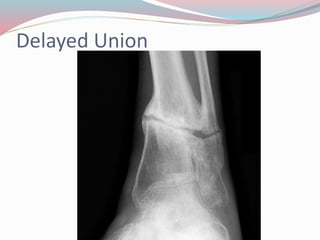

Delayed Union

๏‚— Delayed union